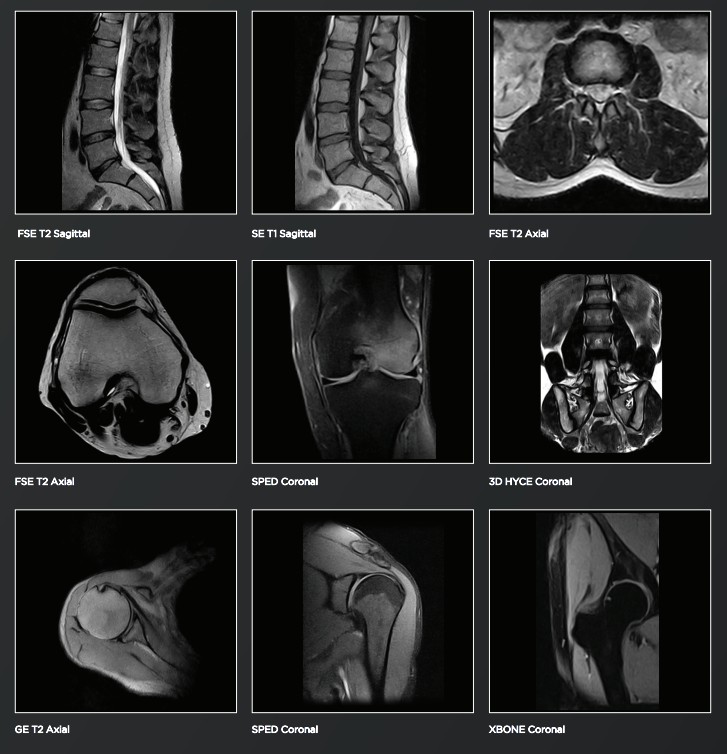

Embedded in G-scan Open, the eXP platform provides advanced software techniques, such as Speed-Up and TR reduction, to reduce scan time and extra sequences designed to improve diagnostic output and accuracy.

- X-Bone & SPED Dixon techniques

With dedicated sequences, such as 3DHYCE for spine nerve roots, 3DSHARC for cartilage and Spin Echo Dixon (SPED), G-scan Open offers exhaustive protocols that can be tailored to specific needs.